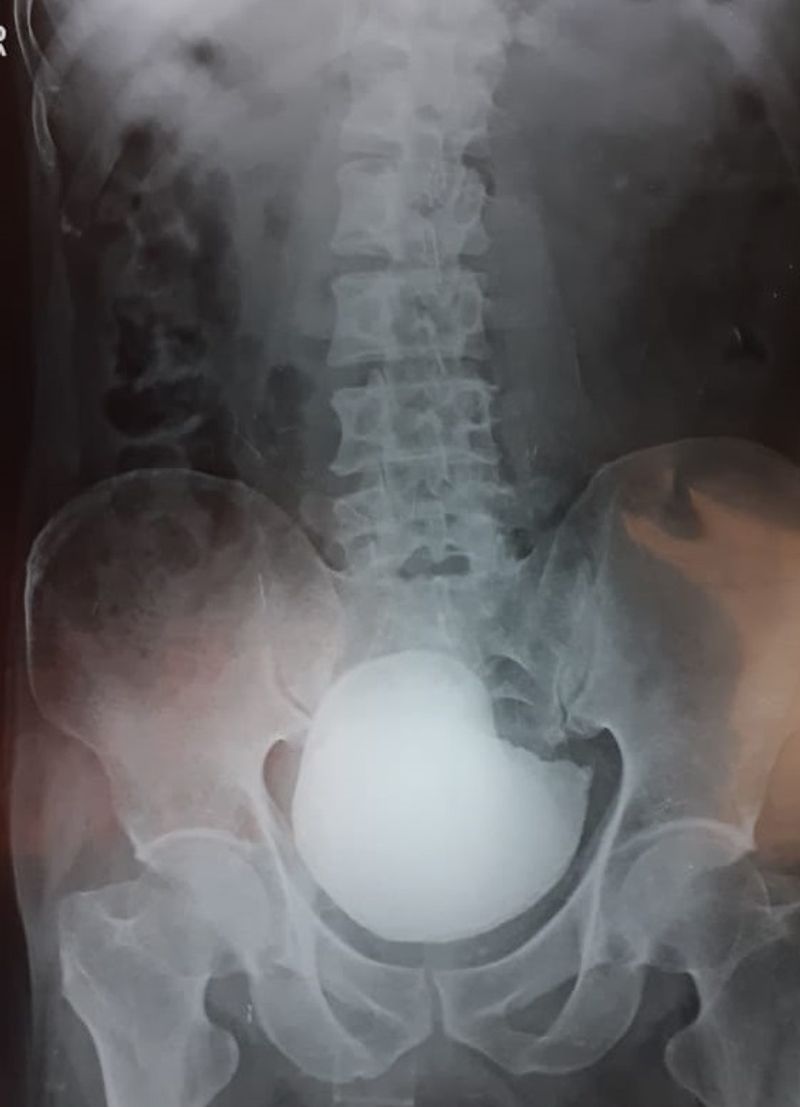

ವಿಜಯಪುರ(ಜೂ.10): ವೈದ್ಯಕೀಯ ಲೋಕದಲ್ಲಿ ಅಪರೂಪದ ಶಸ್ತ್ರಚಿಕಿತ್ಸೆಯನ್ನ ನಗರದ ವೈದ್ಯರು ಮಾಡಿದ್ದಾರೆ. ಹೌದು, ಮೂತ್ರಕೊಶದ ಸಮಸ್ಯೆಯಿಂದ 48 ವರ್ಷದ ವ್ಯಕ್ತಿಯೊಬ್ಬರು ಭಾಗ್ಯವಂತಿ ಆಸ್ಪತ್ರೆಯಲ್ಲಿ ದಾಖಲಾಗಿದ್ದರು. ವೈದ್ಯರು ಎಕ್ಸರೇ ತೆಗೆದು ನೋಡಿದಾಗ ವ್ಯಕ್ತಿಯ ಮೂತ್ರಕೋಶದಲ್ಲಿ ಬೃಹತ್ ಗಾತ್ರದ ಕಲ್ಲೊಂದು ಪತ್ತೆಯಾಗಿತ್ತು.

ವೈದ್ಯಕೀಯ ಭಾಷೆಯಲ್ಲಿ ಗೇಂಟ್ ವೆಸೈಕಲ್ ಕ್ಯಾಲಕ್ಯೂಲಸ್ ಅಥವಾ ಲಾರ್ಜ್ ಯುರಿನರಿ ಬ್ಲ್ಯಾಡರ್ ಸ್ಟೋನ್ ಎಂದು ಈ ರೋಗವನ್ನ ಕರೆಯಲಾಗುತ್ತದೆ. ಮೂತ್ರ ಸರಿಯಾಗಿ ಹೋಗದೇ ಇರುವುದು, ಮೂತ್ರ ತಡೆಯಿಯುವುದರಿಂದ ಈ ಸಮಸ್ಯೆ ಉಂಟಾಗುತ್ತದೆ.

ಹೀಗಾಗಿ ಭಾಗ್ಯವಂತಿ ಆಸ್ಪತ್ರೆಯ ಡಾ. ಅಶೋಕ ಬಿರಾದಾರ ಹಾಗೂ ತಂಡ ಶಸ್ತ್ರಚಿಕಿತ್ಸೆ ಮಾಡುವ ಮೂಲಕ 750 ಗ್ರಾಂ ತೂಕದ ಕಲ್ಲು ಹೊರತೆಗೆಯುವಲ್ಲಿ ಯಶಸ್ವಿಯಾಗಿದ್ದಾರೆ. ವೈದ್ಯಕೀಯ ಲೋಕದಲ್ಲಿ ಇಷ್ಟು ದೊಡ್ಡ ಕಲ್ಲು ಪತ್ತೆಯಾಗಿದ್ದು ಅಪರೂಪ ಪ್ರಕರಣ ಇದಾಗಿದೆ ಎಂದು ಹೇಳಲಾಗುತ್ತಿದೆ.